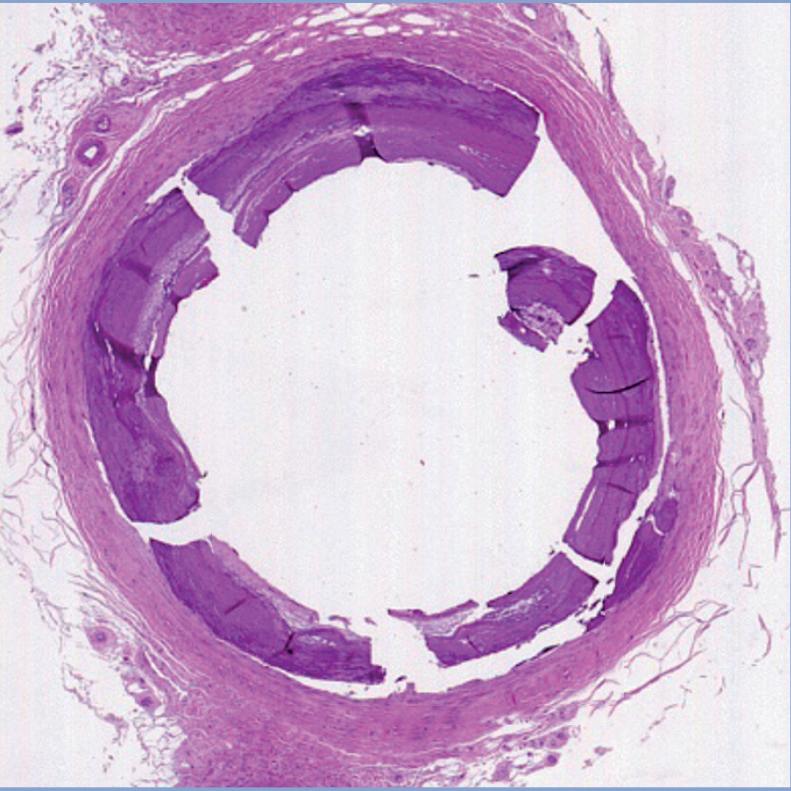

Histology of vessel wall damage after intervention: (left to right) control; plain balloon angioplasty; and orbital atherectomy plus angioplasty

Cue the contemporary backdrop to atherectomy: overuse, questions of harm and worsening results, and mainstream media scrutiny. “We are looking at that right at the vessel wall level,” Roy points out. “We’re taking the legs of real patients who undergo amputation because we were not able to save their legs, characterizing those plaques, then using orbital atherectomy and comparing that with plain balloon angioplasty. We are making real observations of whether it helps in terms of the vessel wall damage, or are we still doing a lot of dissections? Or does it make any difference at all?”

“Once you get your wire across, how do you actually open the blood vessel in an effective way?” Roy continues. “We know that PAD plaques are very variable, and depending on what a plaque is made out of, it’s going to be more or less amenable to a certain device. Each of these devices are made for specific types of plaque. So, if you’re talking about something that’s a big nodular chunk of calcium, that’s going to be different from the eggshell calcium around the perimeter, which is different from soft thrombus, and so on.”